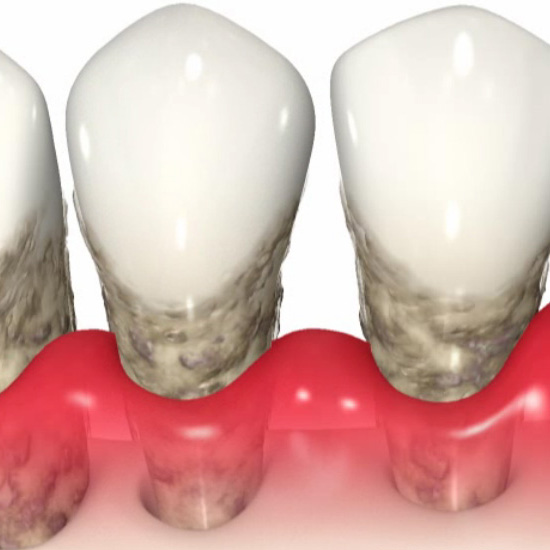

⼝の中にたまった⻭垢(プラーク)が原因で、⻭⾁(⻭茎)の炎症から始まり、

やがては⻭を⽀える⾻を溶かして⻭を失ってしまう病気です。

⻭周病の治療では、原因となる⻭垢(プラーク)を取り除くことが第⼀です。

ポイックウォーターを⽤いて殺菌を⾏いながら、⻭⾯についたプラークや⻭⽯の除去、⻭周ポケット深くに⼊り込んだ⻭⽯やプラークを除去します。

⻭の表⾯に付着している⻭周病菌の巣である「バイオフィルム」を専⽤のカップを装着した回転式機器を⽤いて徹底的に取り除いていきます。⻭の表⾯の着⾊除去にも効果があります。